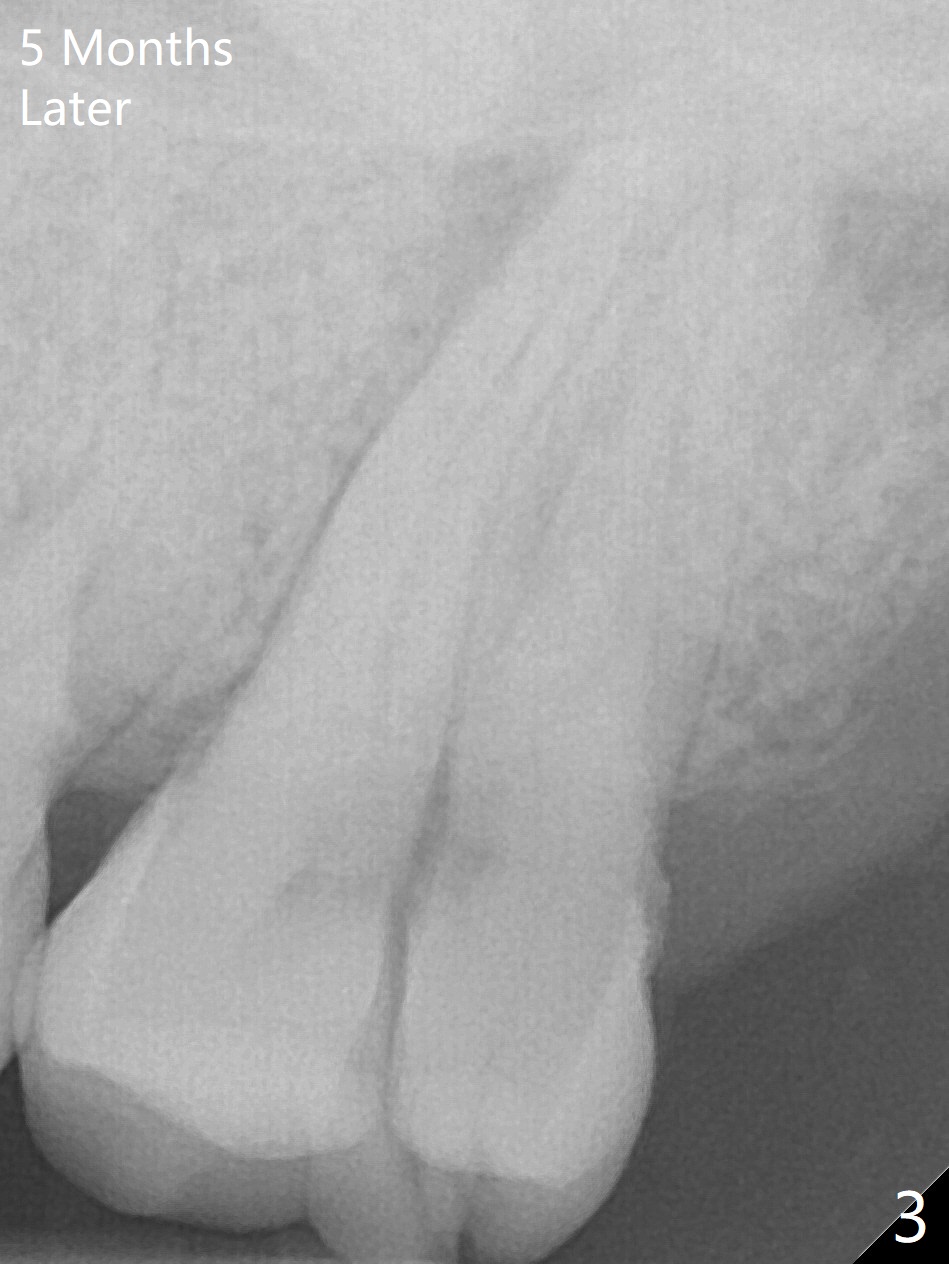

A 44-year-old man presented to clinic with pain of the upper left quadrant (Fig.1), but the affected tooth was not determined until 5 months later (Fig.3,4). Retrospectively the minor crack is visible earlier (Fig.2 arrowheads). It appears that the remaining bone (sinus floor) is limited (Fig.5). Magic Sinus lift or Magic Expanders will be used for sinus lift. Prepare 2-3 pieces of PRF membranes: one or two for sinus lift; the third one to close the socket if primary stability is <30 Ncm.